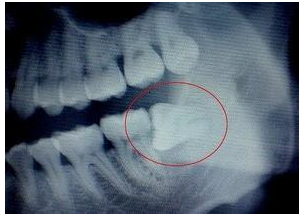

3、3.挤压邻牙:通常患者不知道,而由牙医拍牙片诊断得知。造成患者不舒适或牙疼。这种情况也建议拔除。

5、5.医生确定是阻生齿:这一种类型的牙齿,牙位复杂,拔牙技术也有很高的要求,产生疼痛,那也需要拔除。